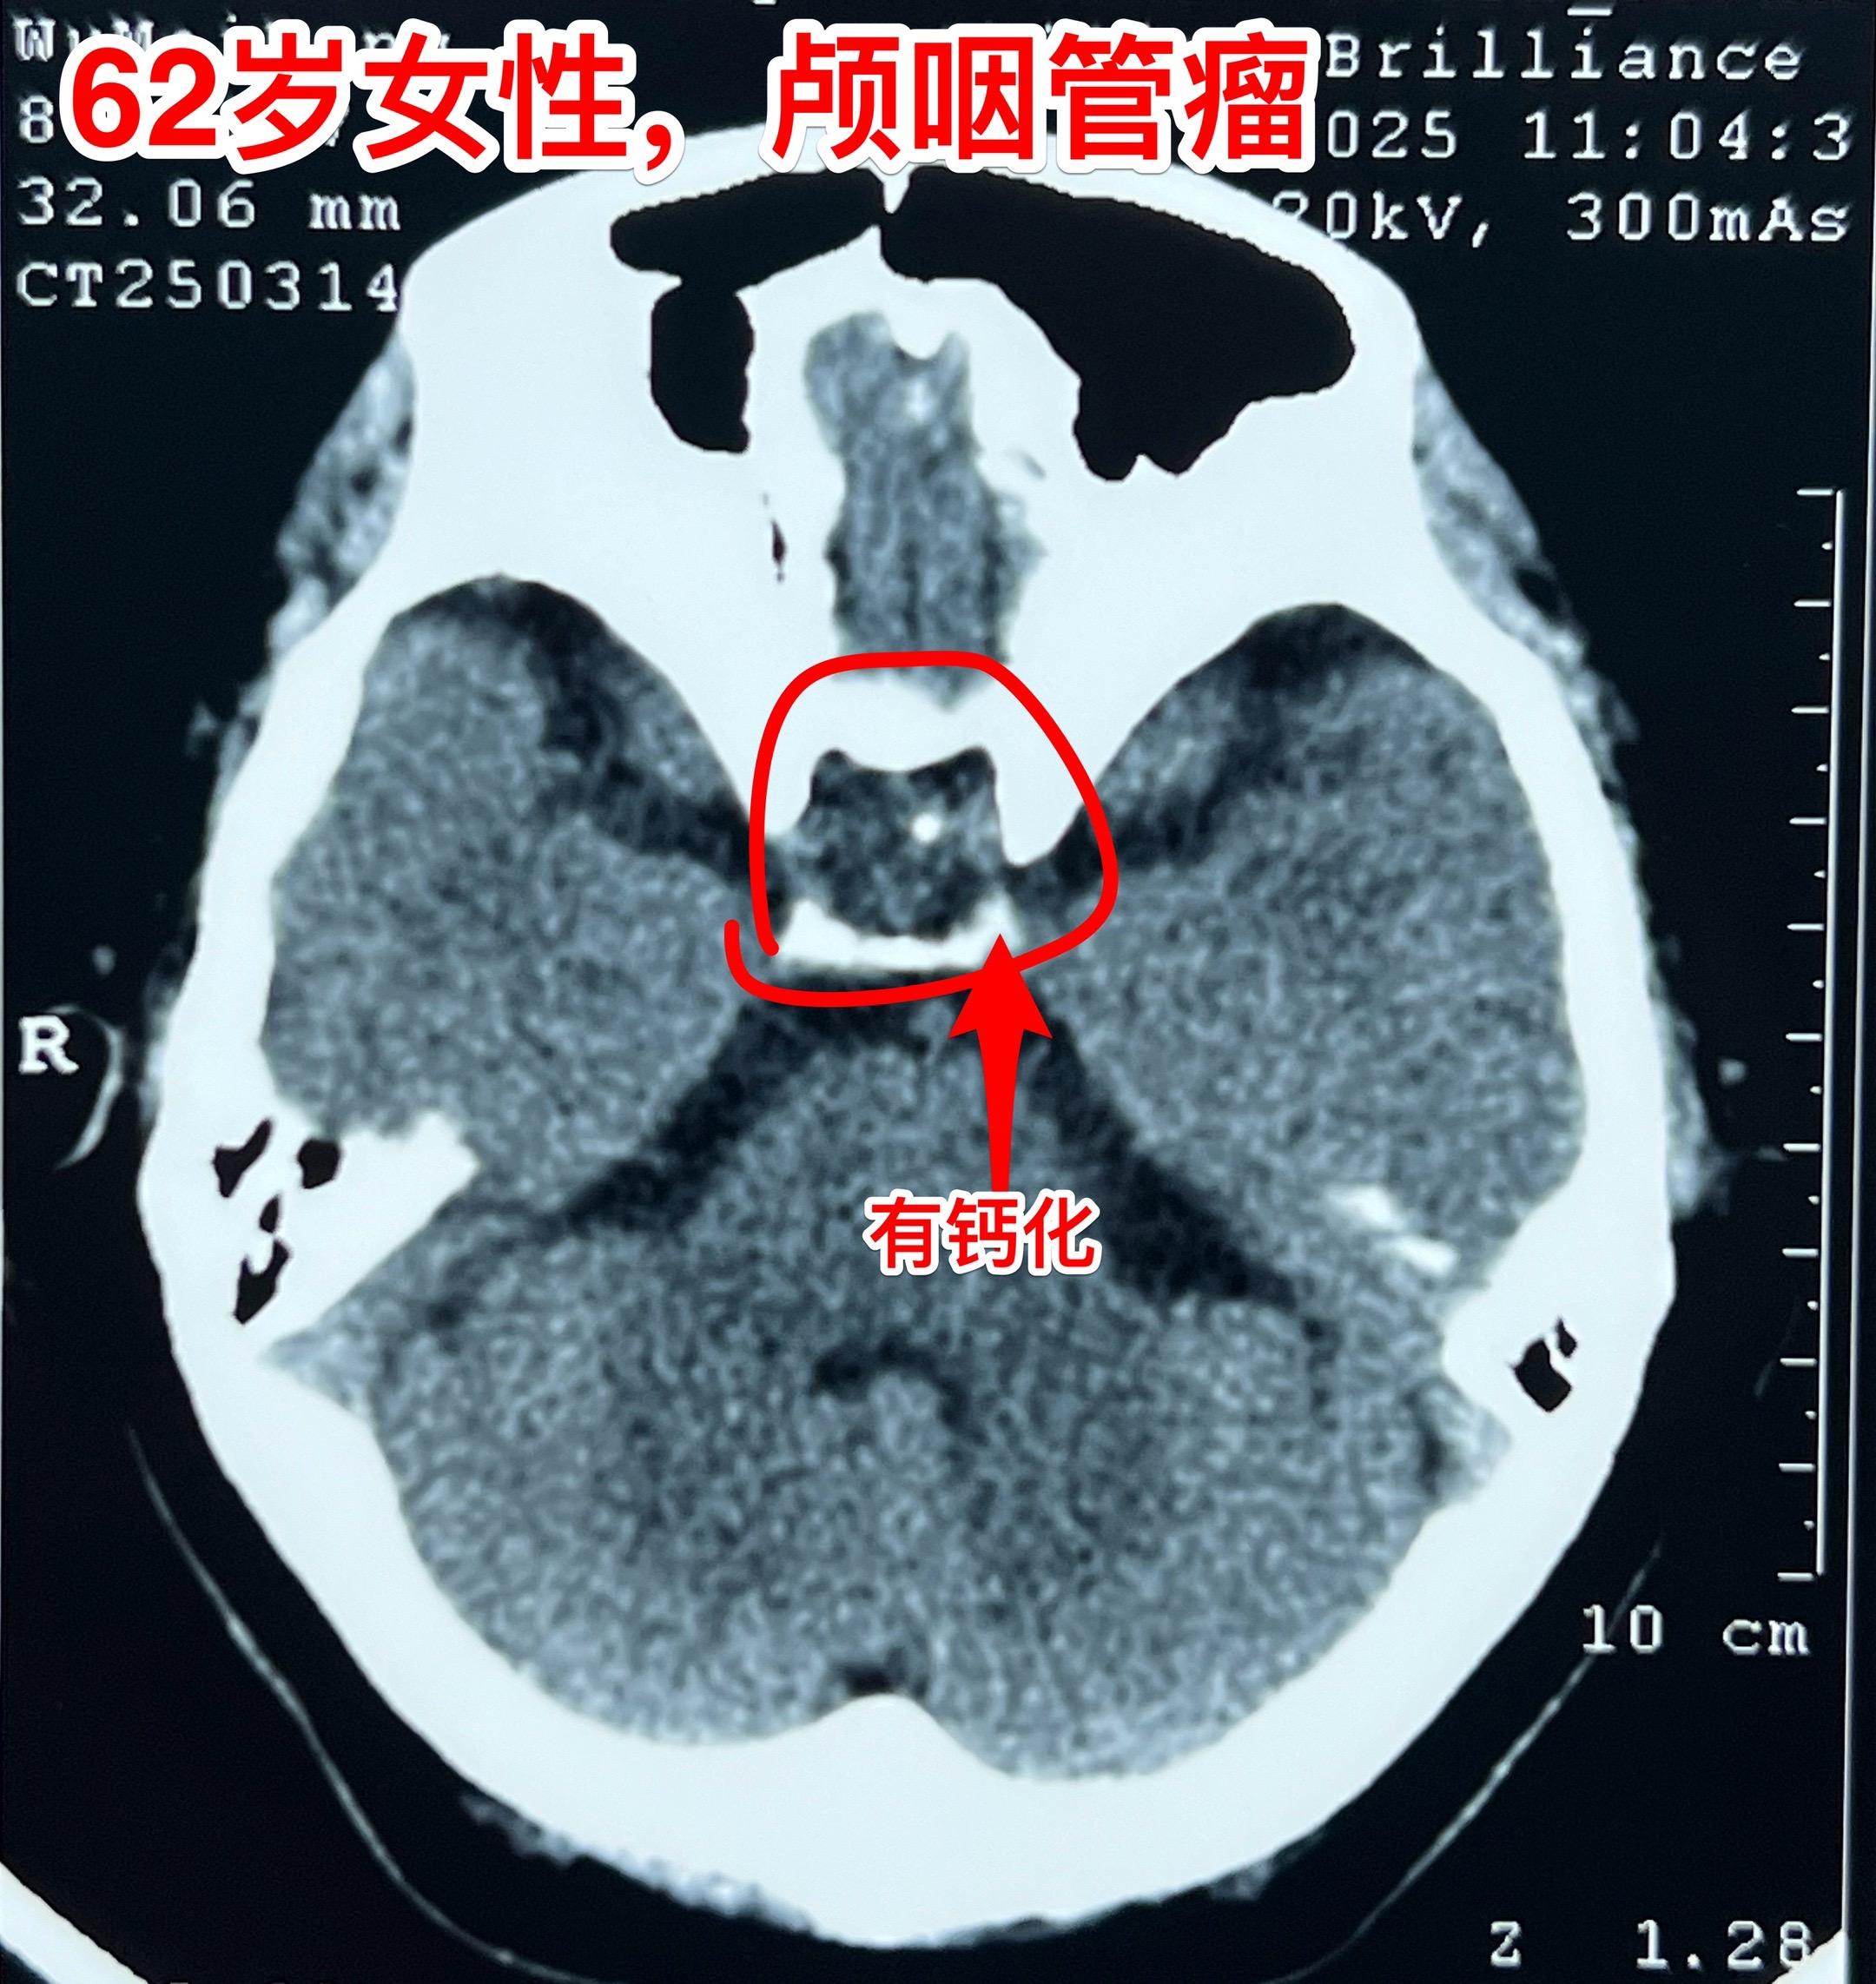

经翼点入路切除颅咽管瘤-不能忘记的入路 经翼点入路切除颅咽管瘤,曾经是广泛使用的一种入路,当然有其优点。近十几年使用这个入路切除颅咽管瘤的机会大大减少了。 对于比较小的鞍上型颅咽管瘤或者自中线偏向侧裂池方向生长的颅咽管瘤,这个入路是很适合的。 3月21日为62岁女性病人切除颅咽管瘤,采用的就是经翼点入路。肿瘤得到完全切除,垂体柄得到保护[强]